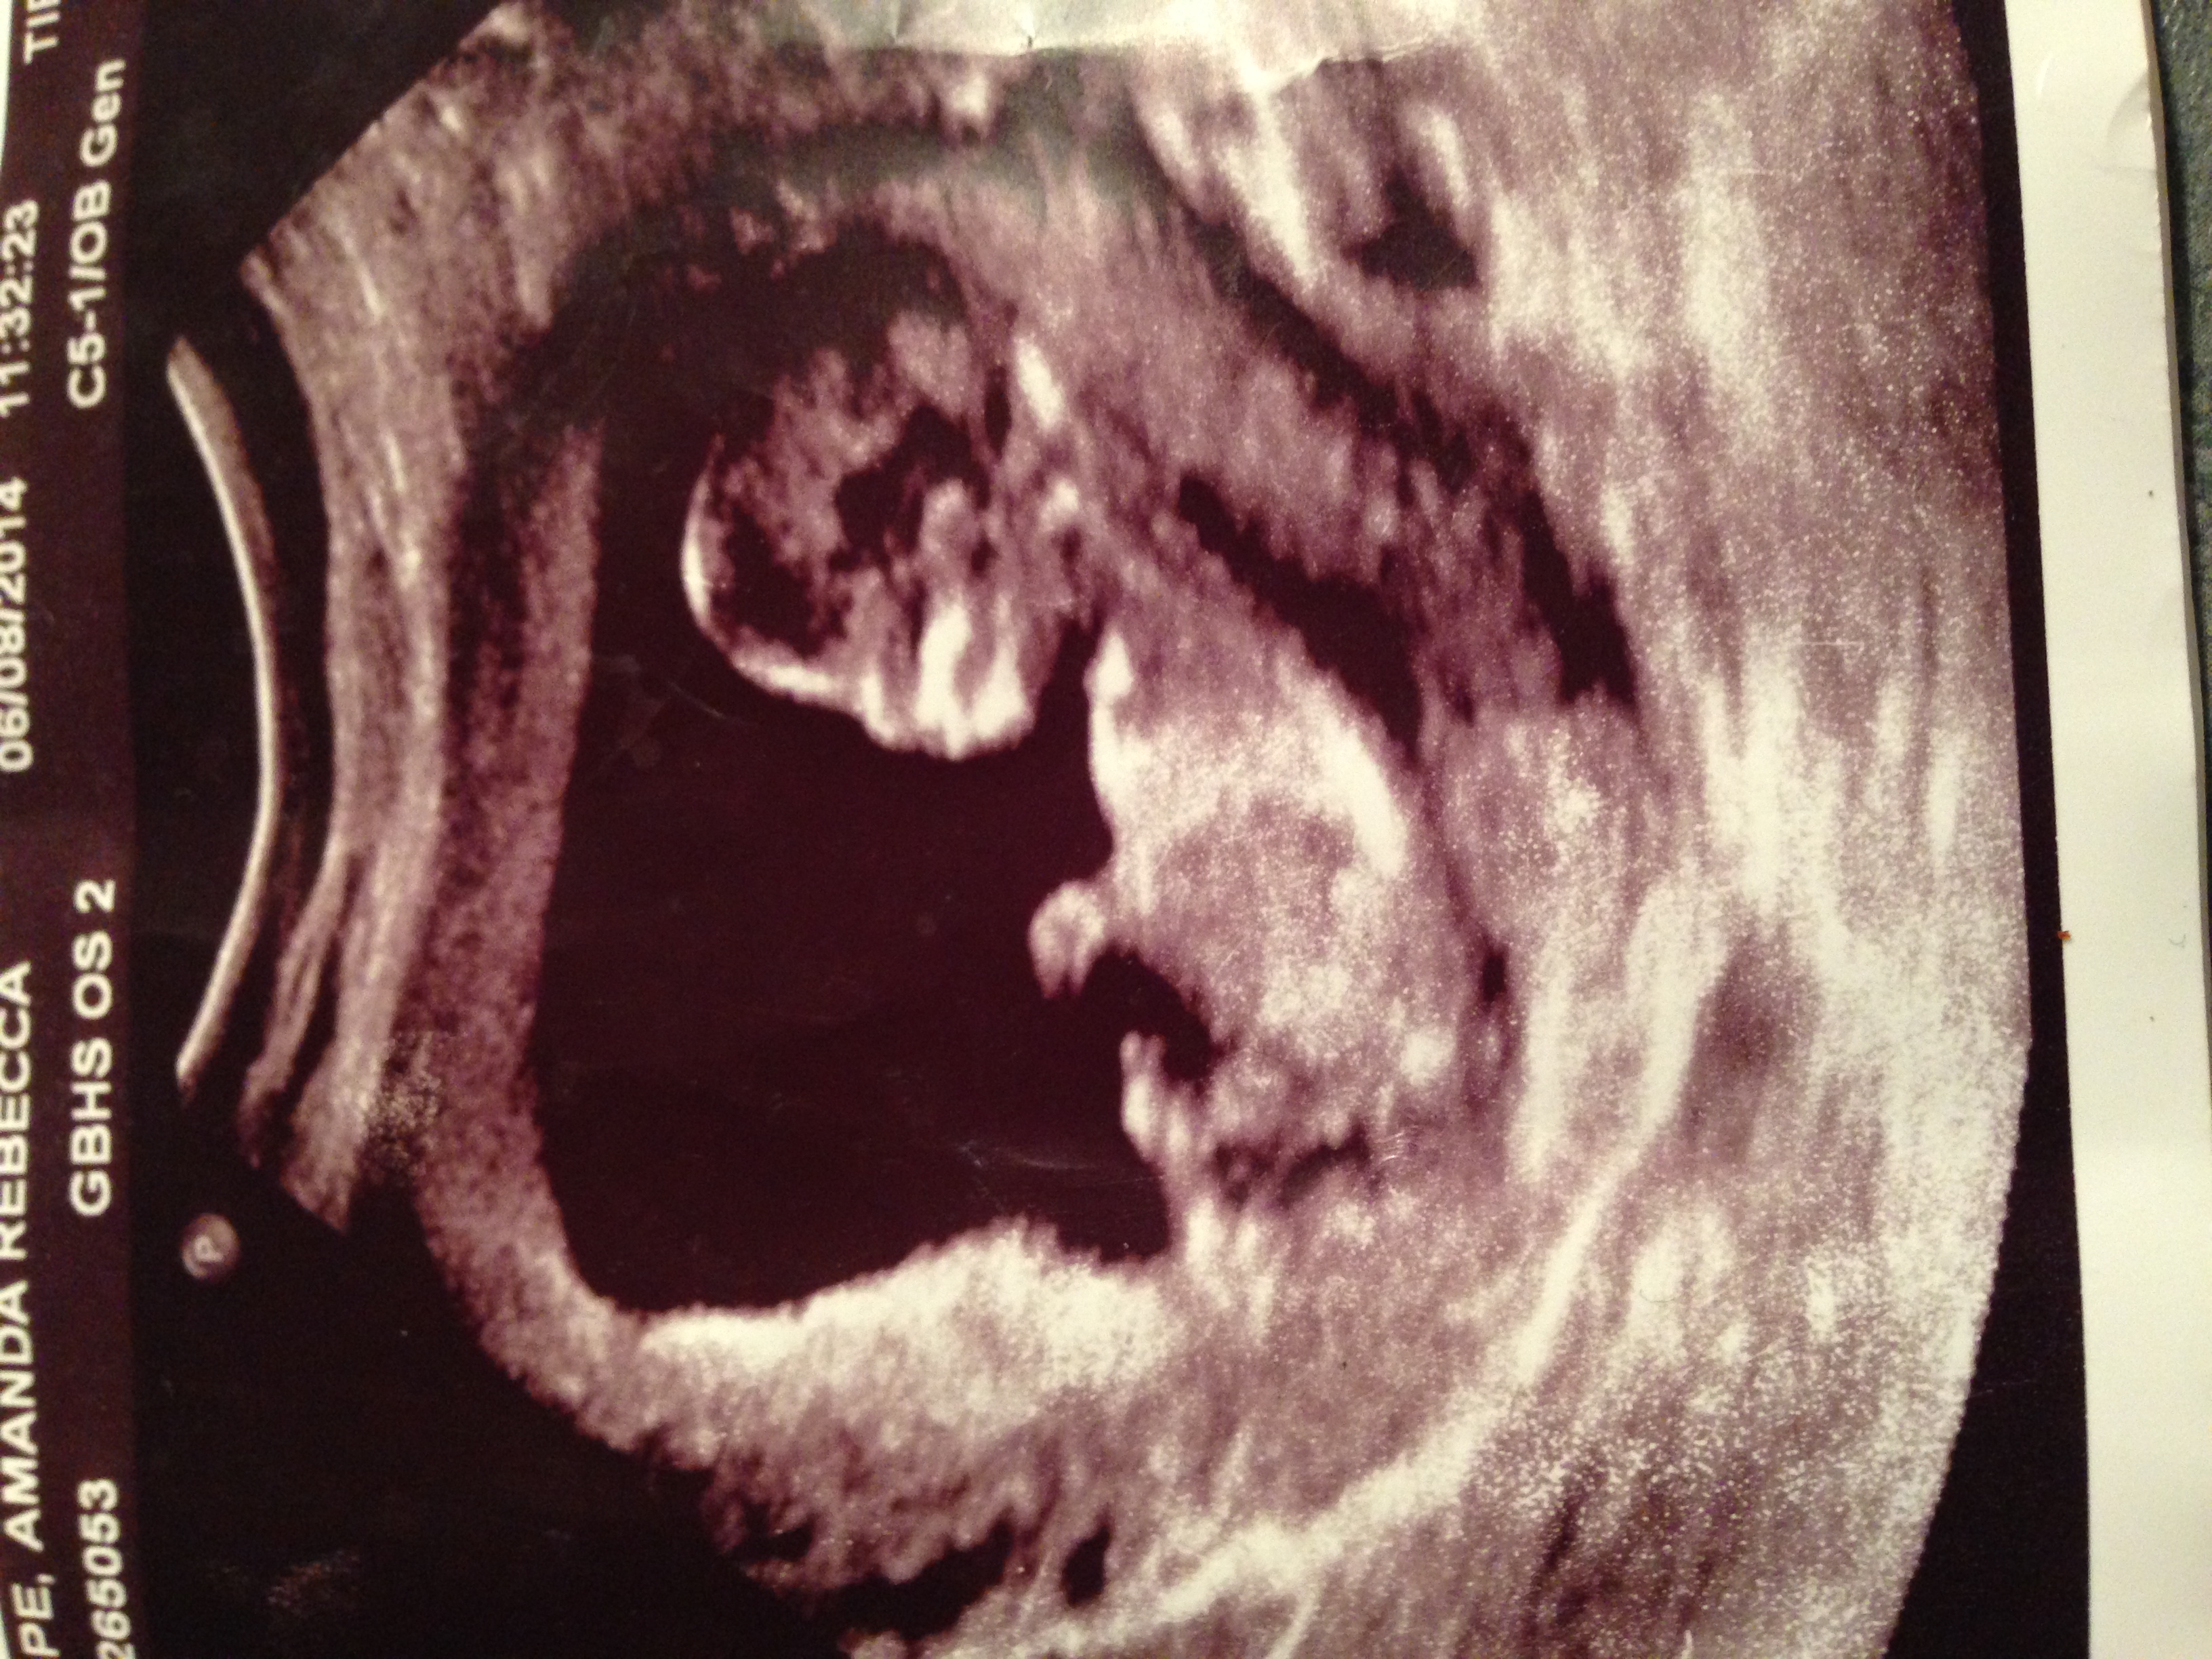

I have posted this photo before but my camera quality was very poor...I just took the same pic with a better camera...This was a 12 week scan...but I believe baby measured over 13 weeks...

I think I see a nub?

Sorry to be annoying, but any clues or is that part of a leg?Attachment 22418Attachment 22418